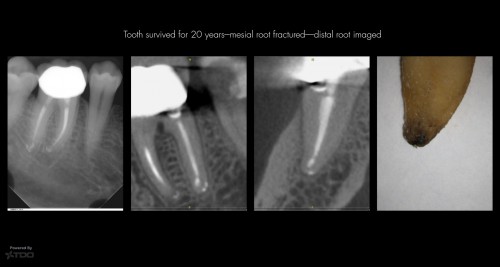

Same “successful” case —same distal root

By Gary Carr / August 13, 2018

Again…a sampling fromn the cemental root surface. The Endodontic Triad people just can’t seem to […]